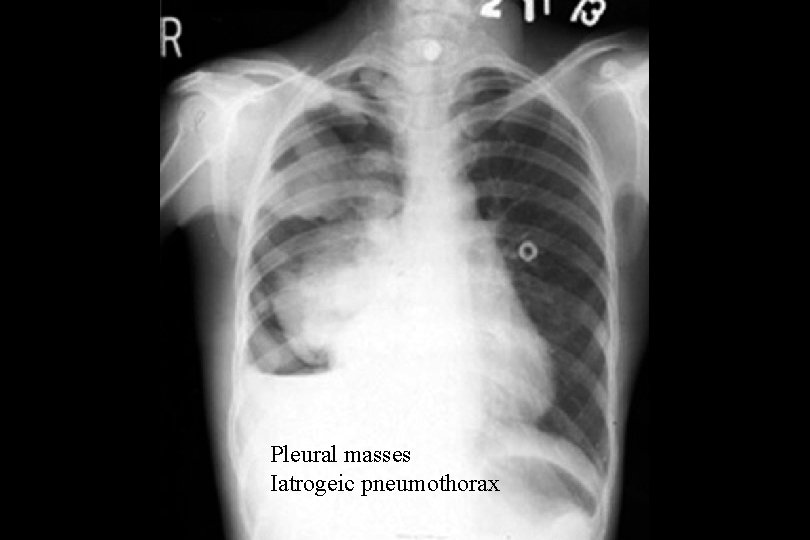

Pleural masses Iatrogeic pneumothorax